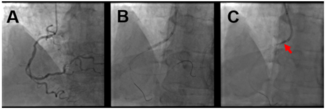

Coronary perforation is a potentially life-threatening PCI complication. We examined the clinical, angiographic, and procedural characteristics, management, and outcomes of coronary perforation at a tertiary care institution.